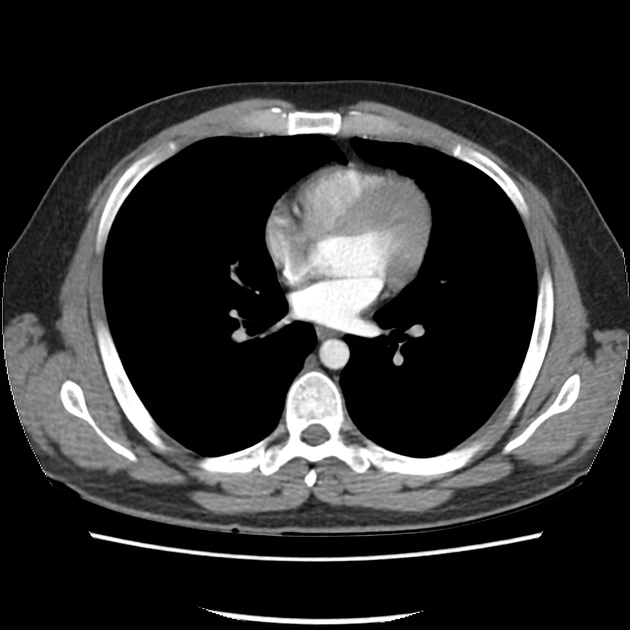

Hình ảnh chụp cắt lớp CT ngực (Computed tomography of the chest)